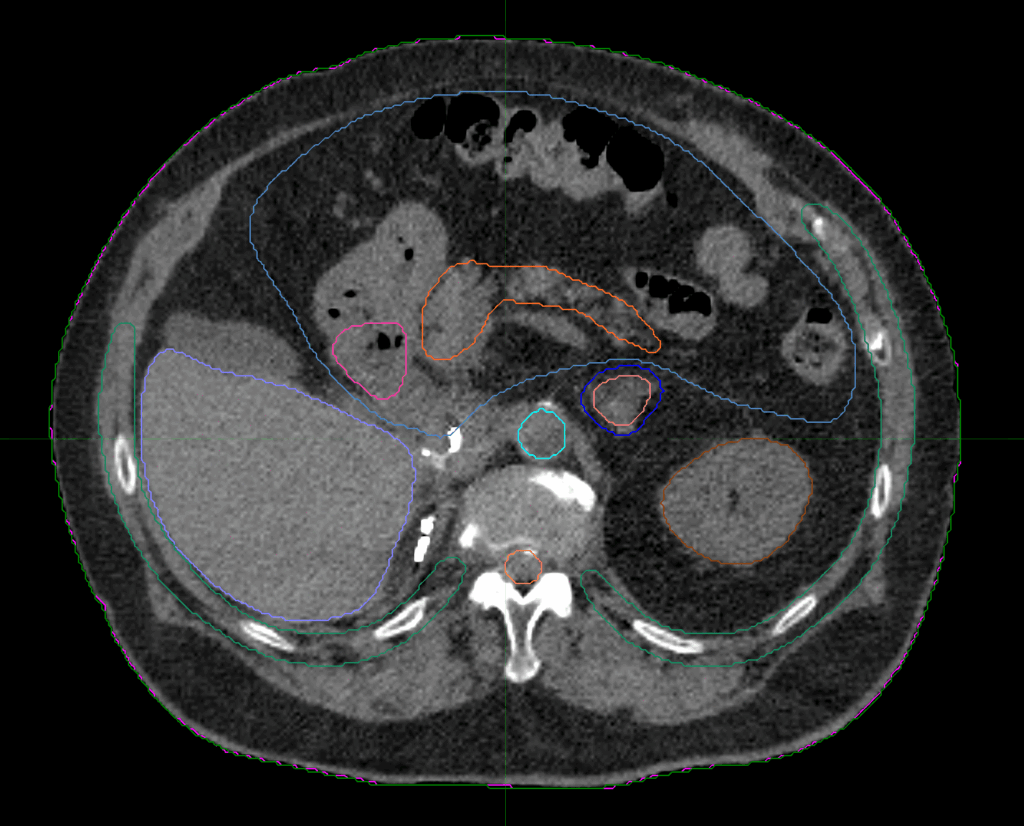

Planning CT Images